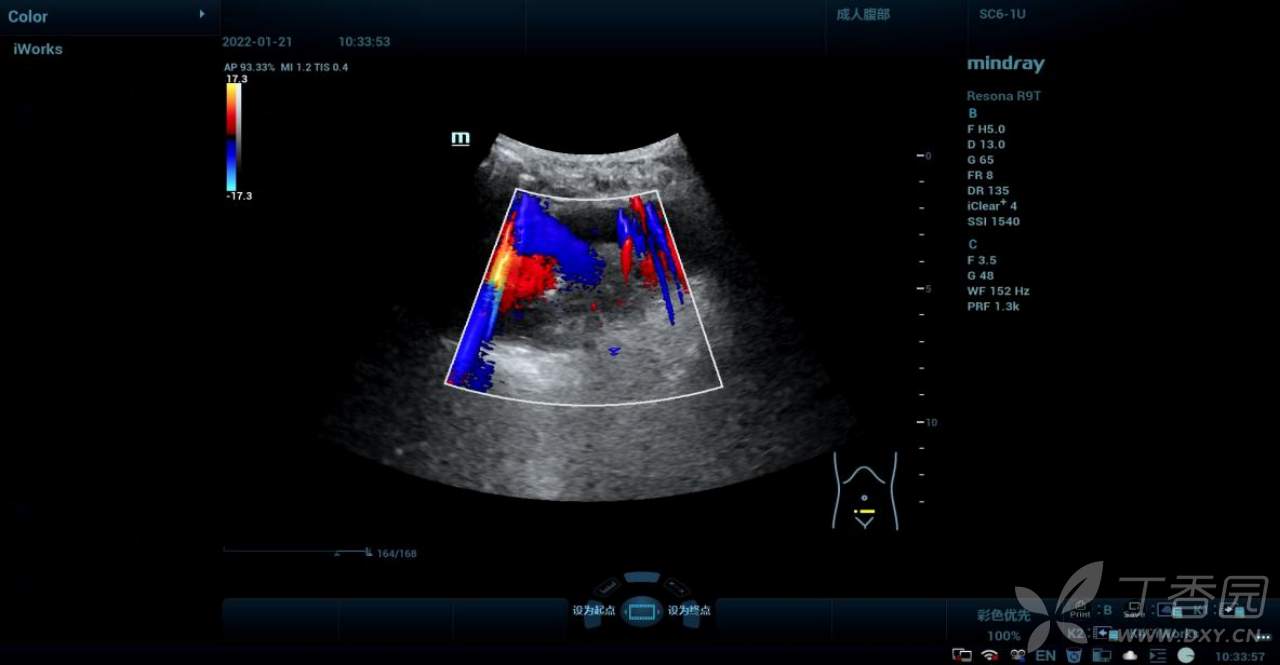

CDFI:其内可见点条状血流信号。